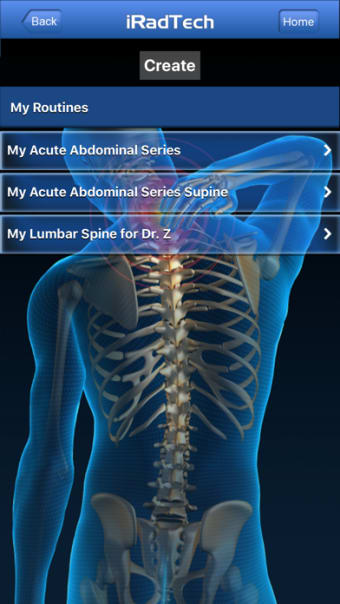

IRadTechè un programma completo per iPhone, che fa parte della categoria 'Medicina'.

Informazioni su IRadTech per iPhone